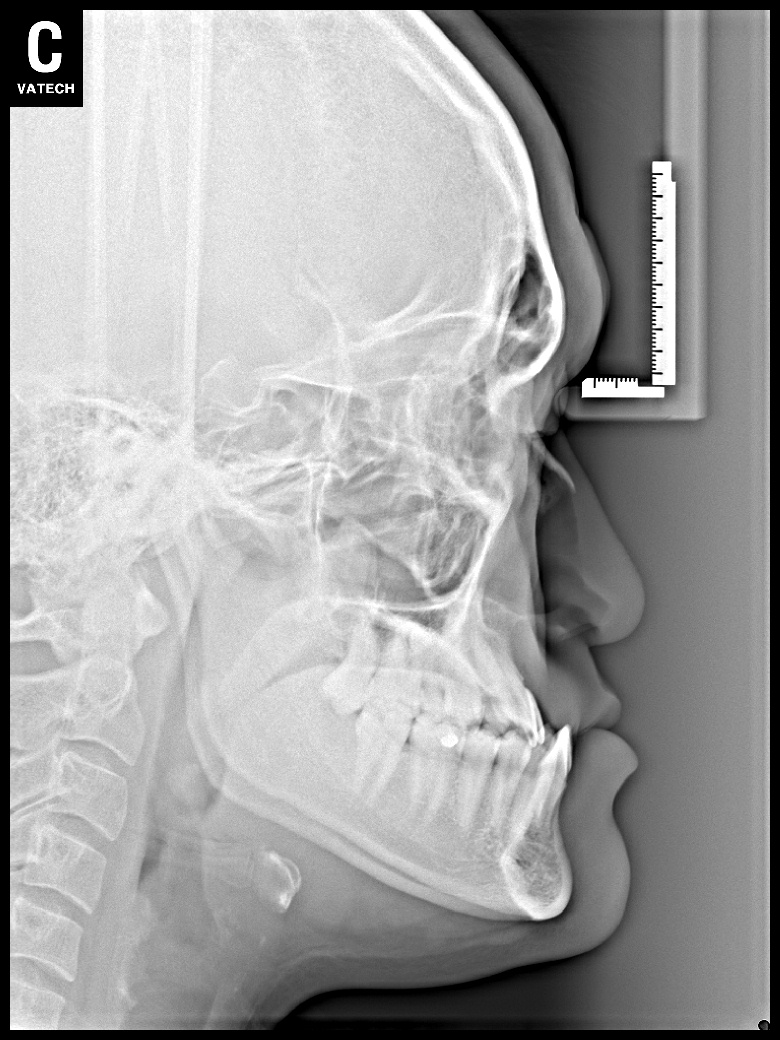

치료 전 사진입니다.